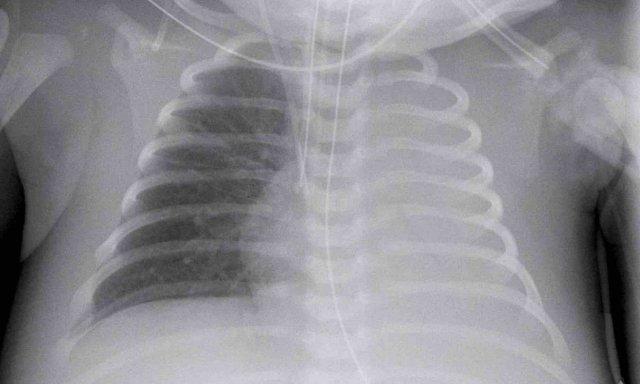

29 tuần + 1, ngày đầu tiên. CPAP.

Nhìn vào hình ảnh lần đầu.

Những phát hiện là gì?

Findings:

- Reticulogranular opacification

of lungs - Air bronchogram

- Consolidation in the right lower lobe

- Heart, vessels and

diaphragm are poorly defined. - Đặt sai vị trí catheter tĩnh mạch rốn (mũi tên), có thể nằm trong tĩnh mạch phổi.

- Nasogastric tube (NG tube) in good position.

Đây là trường hợp nặng của hội chứng suy hô hấp (RDS).

Chẩn đoán phân biệt bao gồm nhiễm trùng phổi do tình trạng đông đặc không đối xứng.